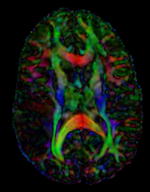

this is the fixed reference image. All images are aligned into this space lleft this is the T2 reference image, serves as target to the DTI baseline, but is itself aligned to the SPGR lleft this is the DTI Baseline scan, to be registered with the T2 this is the DTI tensor image, in the same orientation as the DTI Baseline

Registered DTI superimposed on SPGR and T2 registered (cycles show T1 and T2 and color DTI overlay)